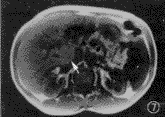

图7~9 男,51岁,酒精型肝硬化,尾叶局灶性脂肪肝(箭头)。图7为FLASH(快速小角度激发) T1WI(同相位,TE 4.1 ms),肝脏尾叶信号略高;图8为FLASH T1WI (离相位,TE 2.2 ms),尾叶信号明显降低;图9为true-FISP T2.WI,尾叶也呈低信号

我们所用的true-FISP T2.W序列选用TE为2.3 ms,在场强为1.5 T的MRI仪中,正相当于化学位移成像的离相位(out of phase)图像[10]。本组病例中有3例合并有局灶性肝脂肪变,在true-FISP T2.WI上呈低信号区域(图7~9),可见不仅梯度回波T1WI可用于化学位移成像,也可利用梯度回波T2.WI进行化学位移成像,诊断脂肪肝、肾上腺瘤、血管平滑肌脂肪瘤等水脂混合病变。